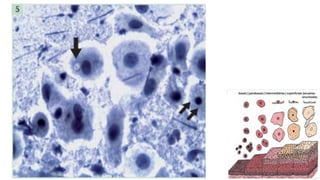

Trofismo do Epitélio

Epitélio Hipertrófico Epitélio HipotróficoEpitélio Normotrófico Epitélio Atrófico

Os núcleos são redondos ou ovais, com alguma variação do

tamanho, cromatina finamente granular exibindo cromocentros

ou nucléolo.